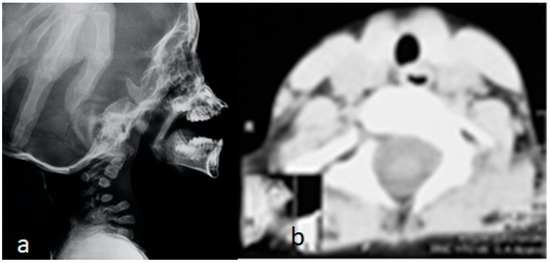

A 2-year-old boy with Larsen syndrome became tetraplegic after minor trauma (jumping down from the sofa). Halo traction with 1 kg was used in the local emergency trauma center, and then after 1 week he was transferred to Ilizarov Center with minor neurological improvement. The lateral skull and spine radiograph showed hypoplastic and maldevelopment of the cervical spine associated with C1-2 instability and apparent kyphotic deformity with C4 body hypoplasia. The size of the cervical spinal canal was normal. So SCIWORA (spinal cord injury without radiographic-like) was a bit confusing due to laxity. But nevertheless, the kyphotic deformity was highly evident, and therefore the mechanism of cord trauma was expected (Figure 8a). An axial reformatted CT scan confirmed the hypoplasia of the vertebral body of C4 (Figure 8b).

Figure 8.

(a,b): Lateral skull and spine radiograph showed hypoplastic and maldevelopment of the cervical spine associated with C1–2 instability and apparent kephotic deformity with C4 body hypoplasia. The size of the cervical spinal canal is normal. So SCIWORA (spinal cord injury without radiographic-like) was a bit confusing due to laxity. But nevertheless, the kyphotic deformity was so evident. and therefore, the mechanism of cord trauma was expected (Figure 6a). Axial reformatted CT scan confirmed the hypoplasia of the vertebral body of C4 (b).